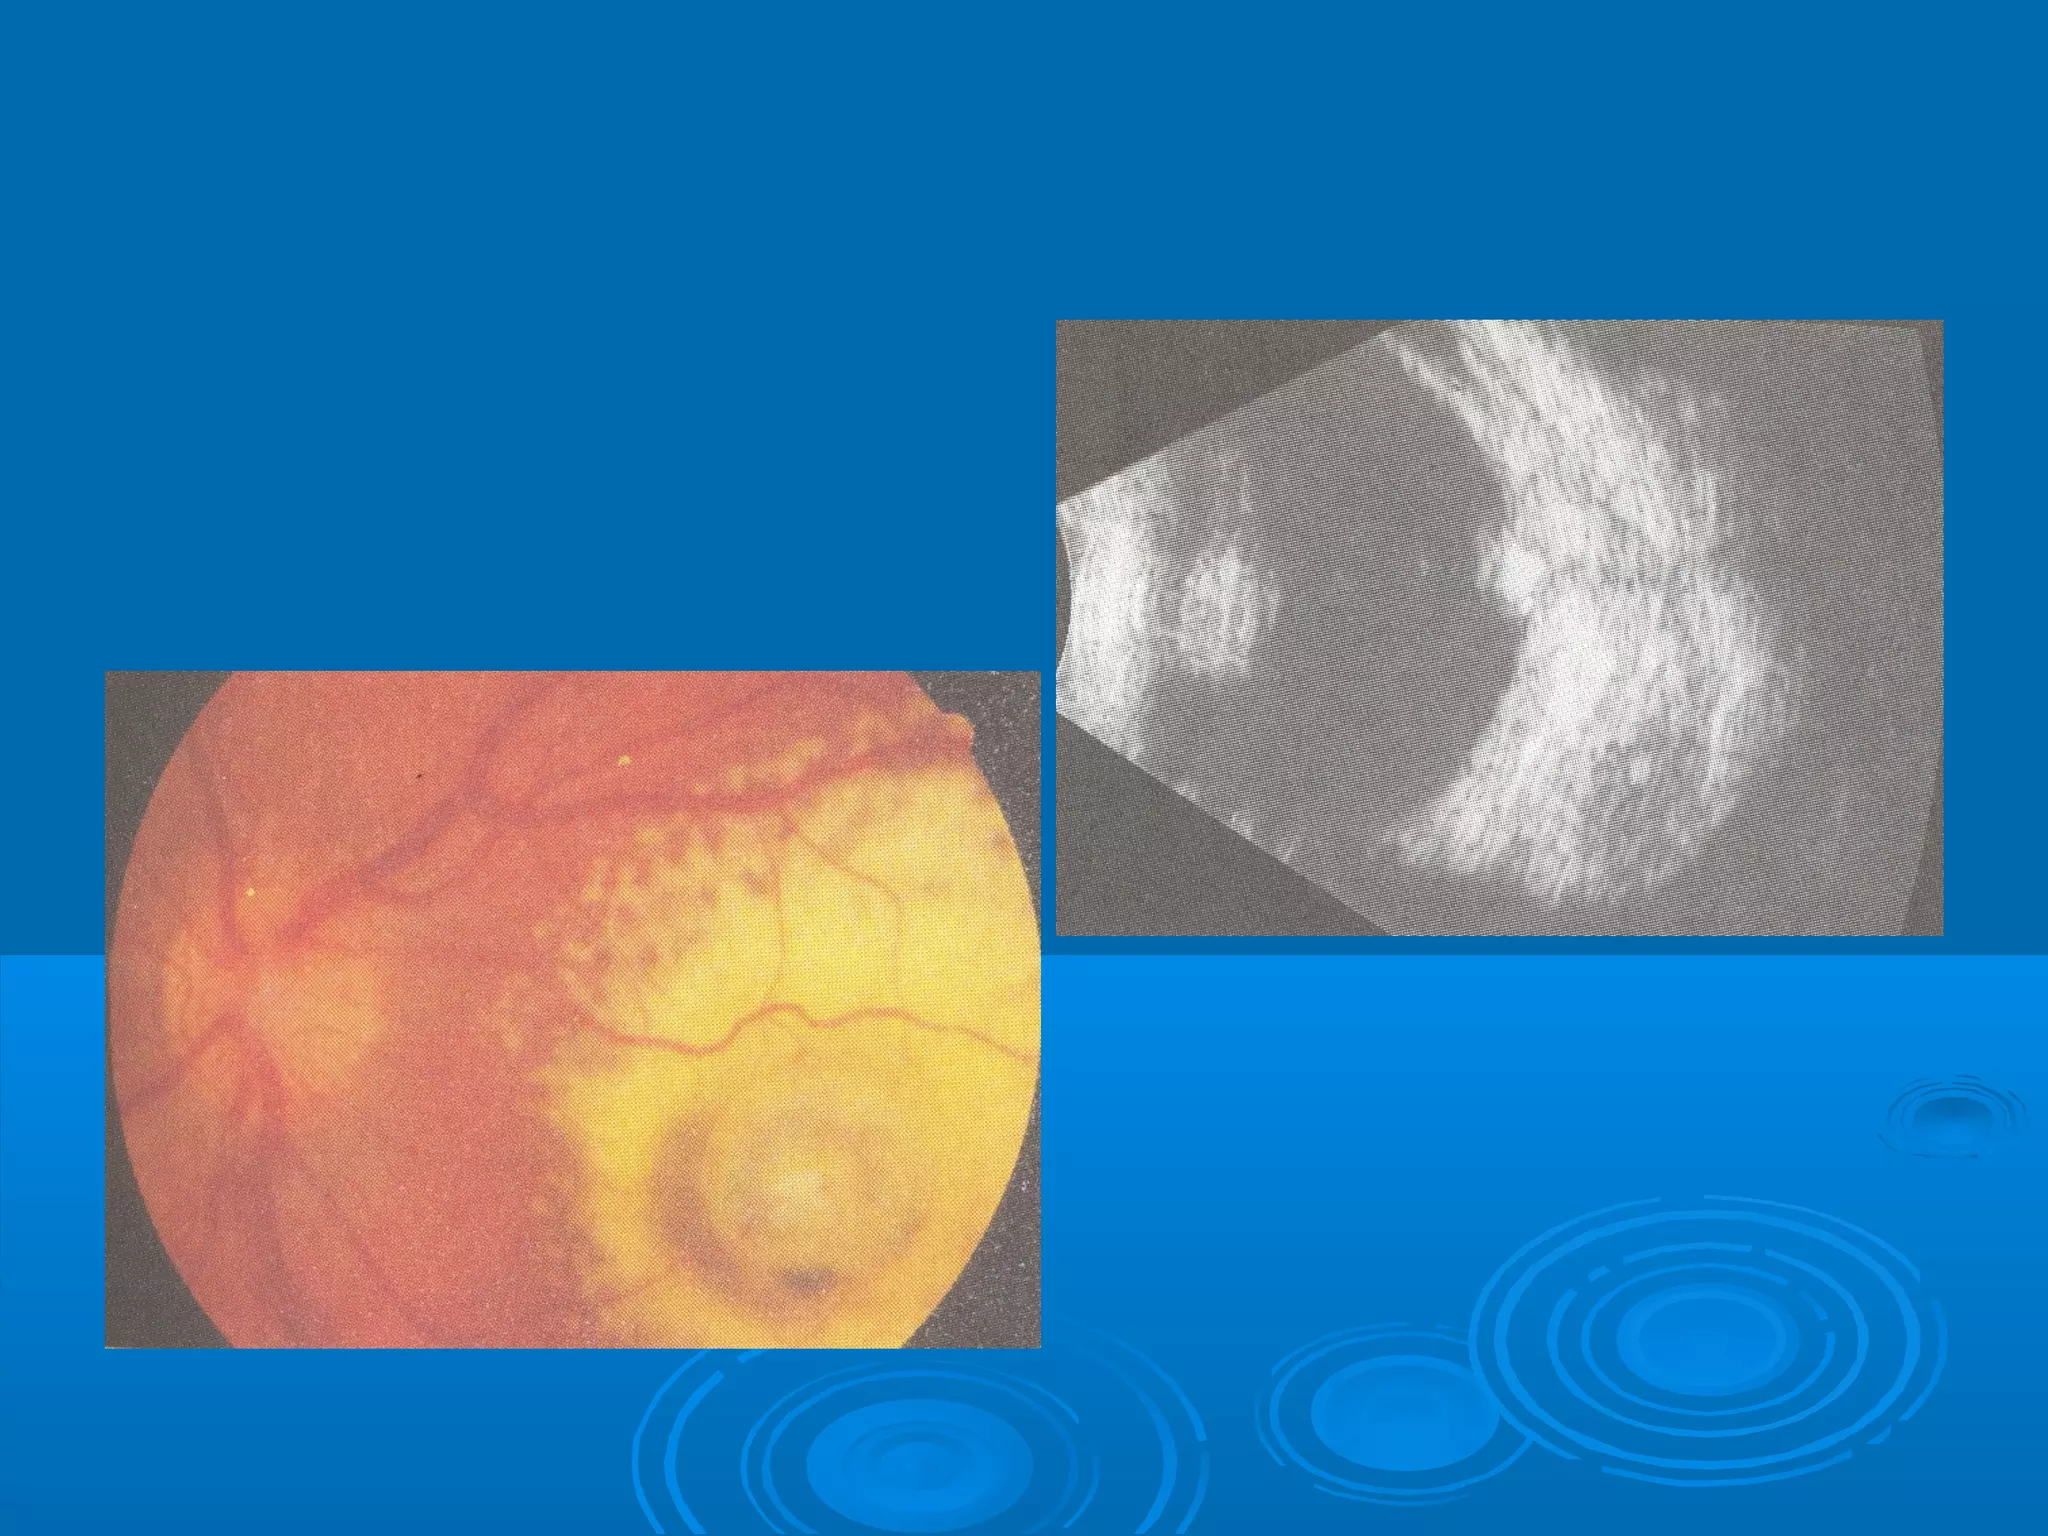

Болезнь Коатса - это идеопатическое заболевание, характеризующееся полиморфными изменениями сосудов сетчатки с массивной экссудацией, чаще всего у детей и подростков, с преобладанием среди мальчиков. Эпидемиология показывает, что заболевание проявляется, как правило, в возрасте 8-16 лет, но возможно его обнаружение и у взрослых. Основные проявления включают ретинальные аномалии, субретинальную экссудацию и постепенно прогрессирующую потерю зрения.